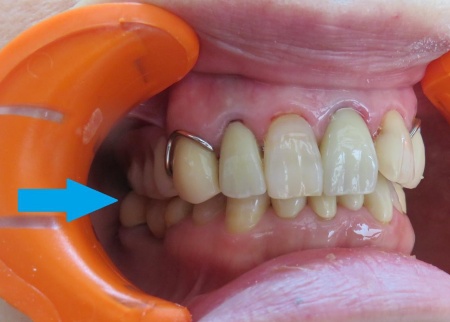

拝見したところ、上の奥歯には左右とも部分入れ歯が装着されていました。

また、入れ歯と噛み合う下の奥歯には、陶器の一種で強度が高いセラミックの被せ物が装着されています。

詳しい検査を行った結果、下奥歯のセラミックの被せ物の影響で、噛み合っている上の入れ歯がすり減っていることが判明しました。

入れ歯の人工歯がすり減っています。